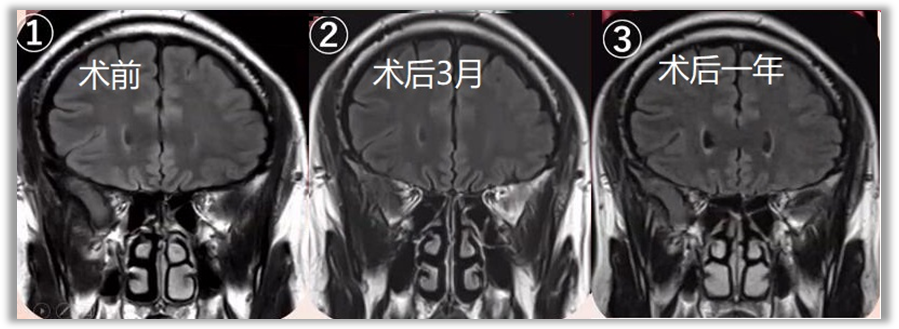

▼术前、术后3月、术后一年鼻腔粘膜对比。可见该术式保留大部分鼻腔粘膜及鼻甲,不破坏鼻腔的通气和鼻窦引流功能。

![]()

图片引自日本Masahiro Shin教授手术录像